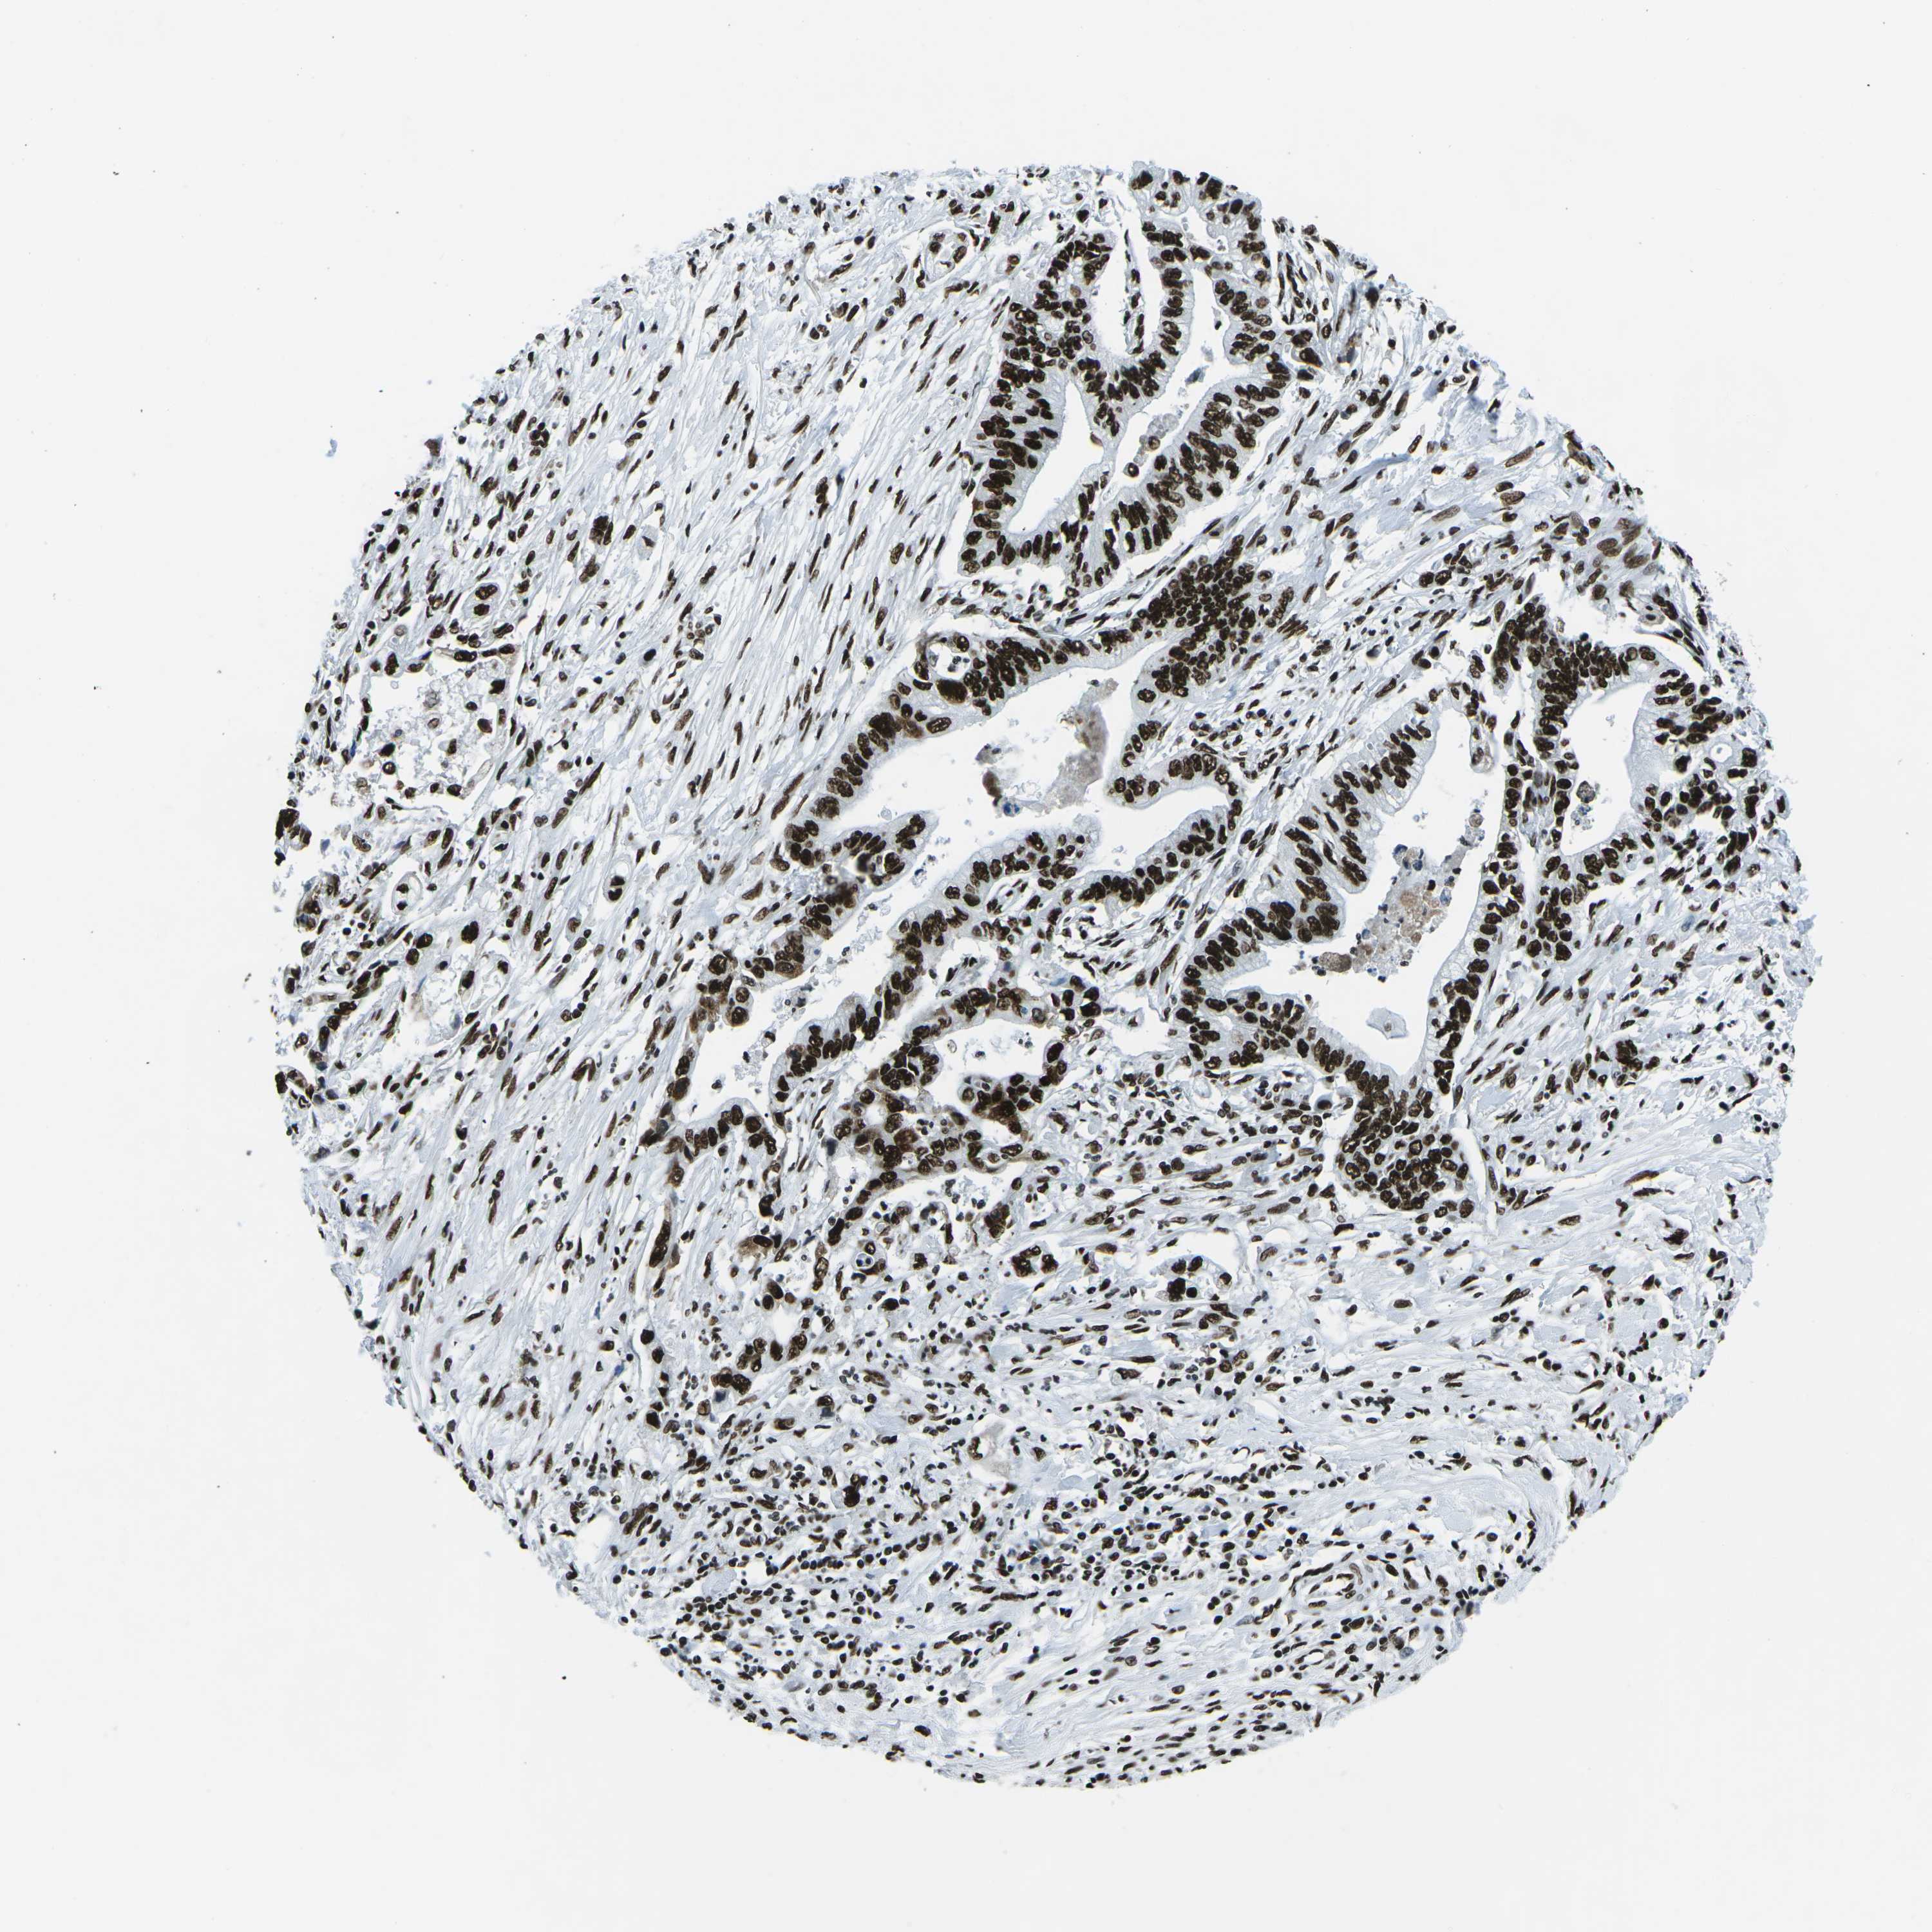

PANCREATIC CANCER - Protein expressioni

A mouse-over function shows sample information and annotation data. Click on an image to view it in a full screen mode. Samples can be filtered based on level of antibody staining by selecting one or several of the following categories: high, medium, low and not detected. The assay and annotation is described here.

Note that samples used for immunohistochemistry by the Human Protein Atlas do not correspond to samples in the TCGA dataset.

Antibody stainingi

Antibody staining in the annotated cell types in the current human tissue is reported as not detected, low, medium, or high, based on conventional immunohistochemistry profiling in selected tissues. This score is based on the combination of the staining intensity and fraction of stained cells.

Each image is clickable and will lead to virtual microscopy that enables deeper exploration of all samples and also displays staining intensity scores, fraction scores and subcellular localization as well as patient and tissue information for each sample.

Antibody HPA051748

Antibody HPA052661

Antibody CAB016326

Staining

High

Medium

Low

Not detected

Intensity

Strong

Moderate

Weak

Negative

Quantity

>75%

75%-25%

<25%

None

Location

Nuclear

Cytoplasmic/membranous

Cytoplasmic/membranous,nuclear

Adenocarcinoma, NOS